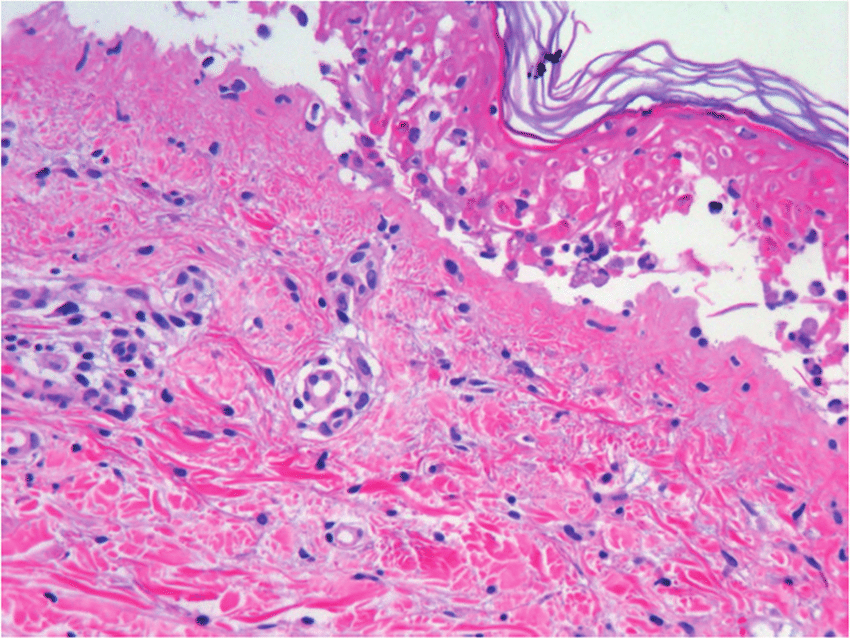

En general, su etiología y presentación son consensuadas, definiéndose como una necrólisis generalizada de la epidermis que se produce como una respuesta inmune descontrolada a un fármaco específico o a uno de sus metabolitos, destacando el cotrimoxazol y el alopurinol como los más importantes. Esta necrólisis conduce a un desprendimiento masivo de la capa epidérmica de la piel, con mayor incidencia en el torso, miembros superiores y cara. Eur. Burn J. 8 agosto 2022